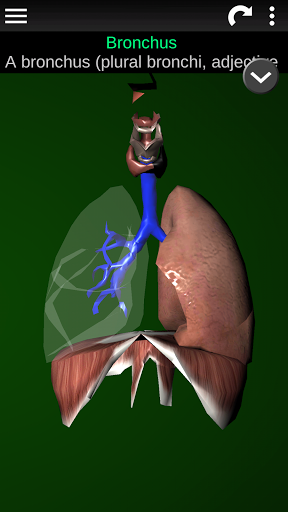

Internal Organs in 3D Anatomy لـ Vodafone Smart N9 Lite

(الأجهزة الداخلية في)

Organs 3D Anatomy 2.0.12

يمكنك هنا تنزيل ملف حزمة تطبيق أندرويد "Internal Organs 3D Anatomy" الخاصة بجهازVodafone Smart N9 Lite مجانًا، نسخة ملف حزمة تطبيق أندرويد - 3.4 للتحميل على Vodafone Smart N9 Lite اضغط ببساطة على هذا الزر. إنه سهل وآمن. نحن نقدم فقط ملفات حزمة تطبيق أندرويد الأصلية. إذا انتهكت أية مواد موجودة في الموقع حقوقك قم بإبلاغنا من خلال